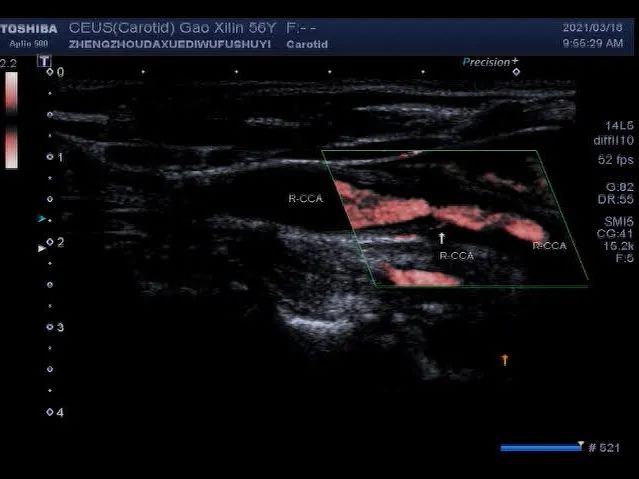

▲ 超声造影显示:红色箭头所指处为斑块新生血管

颈动脉斑块超声造影(CEUS)则是通过注射造影剂来显示颈动脉局部有无斑块、斑块大小、位置、回声、斑块内有无新生血管及新生血管含量、分布;颈动脉管腔局部有无狭窄及狭窄程度;颈动脉支架位置、局部有无再狭窄等。